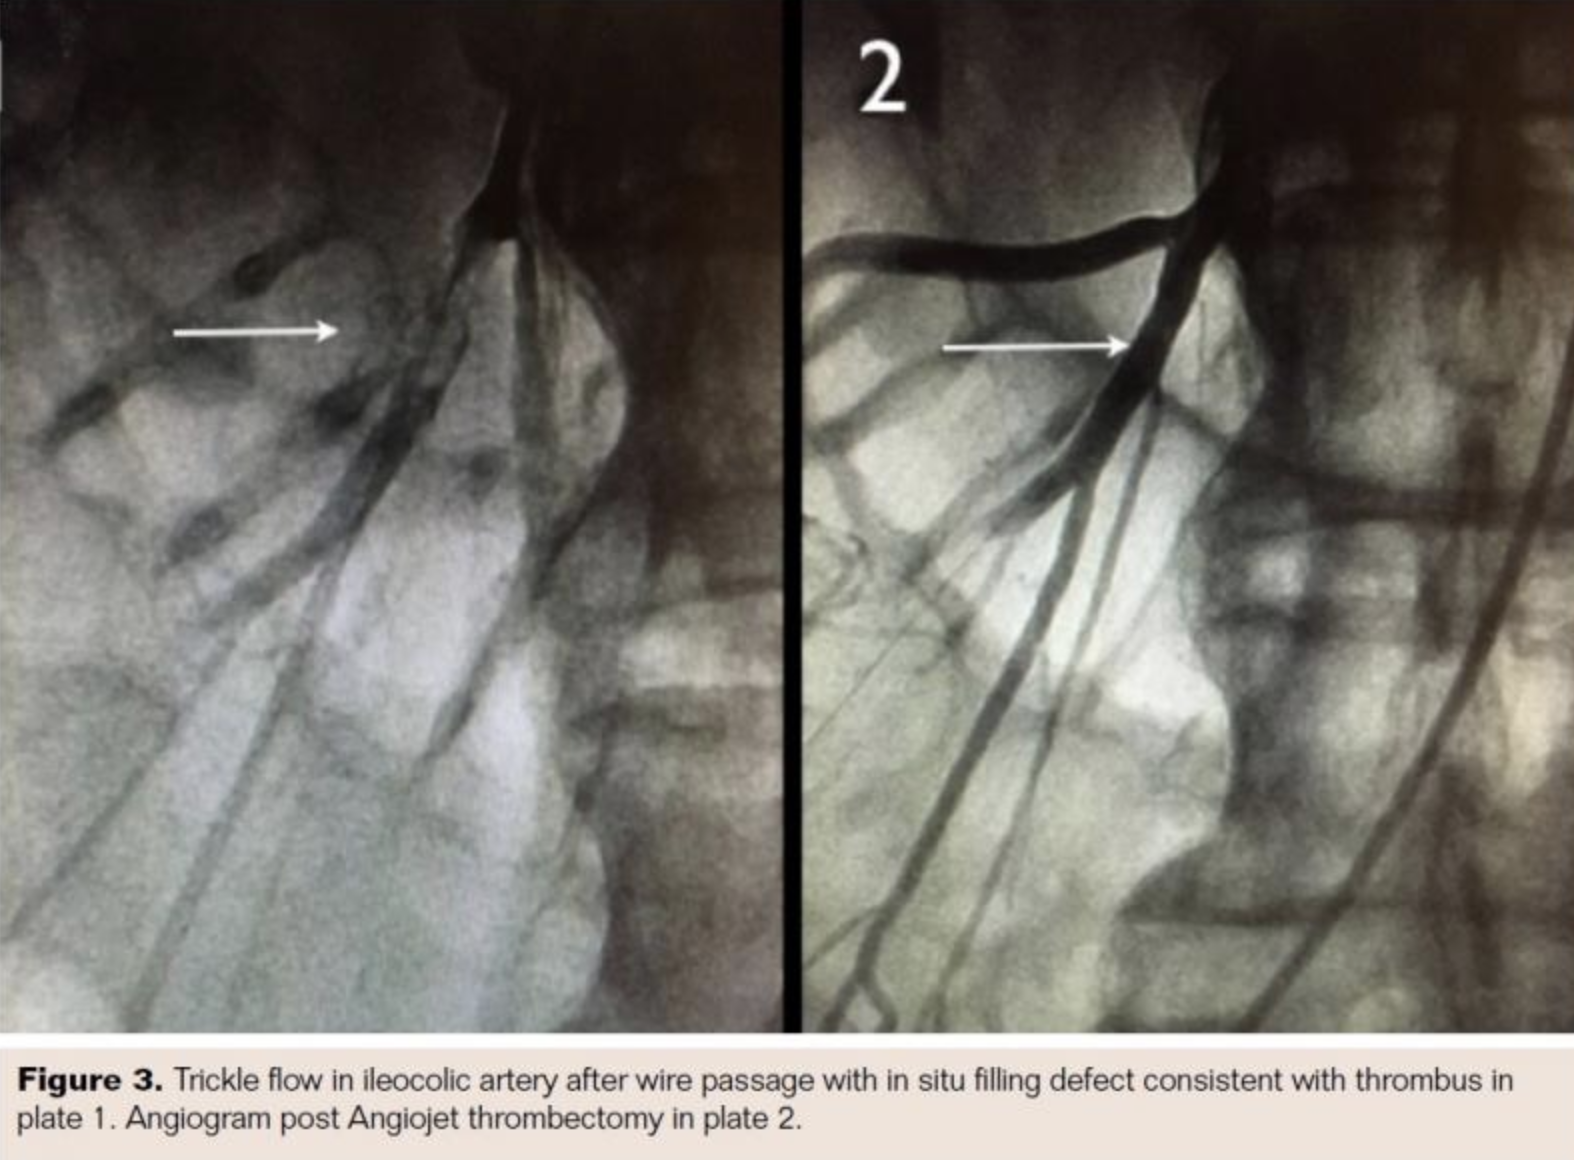

Laboratory evaluation in the emergency department showed a white blood cell (WBC) count of 9,600/μL with 82.9% neutrophils, creatinine 1.3 mg/dL, glucose 152 mg/dL, bilirubin 1.2 mg/dL, lipase 119 U/L, INR 1.6, plasma thromboplastin time 27 seconds, and lactate 0.92 mmol/L. A computerized tomography (CT) scan of the abdomen and pelvis with and without contrast and with 3D reconstruction was performed (Figure 1). There was no abdominal aneurysm or dissection. There was a filling defect in the superior mesenteric artery consistent with thrombus. There was no bowel wall thickening or evidence of pneumatosis. The patient was treated with intravenous fluids, intravenous heparin 4000 U bolus followed by heparin drip, intravenous hydromorphone 0.5 mg every 4 hours as needed, intravenous levofloxacin 500 mg daily, intravenous metronidazole 500 mg every 8 hours, and ondansetron 4 mg every 4 hours as needed.

The patient was taken for urgent angiography due to rapid rise in biomarkers reflecting early bowel necrosis. Right femoral artery access was obtained and cannulated with a 6 Fr sheath. A 4 Fr internal mammary catheter was used to cannulate the superior mesenteric artery (SMA). The catheter was advanced into the proximal segment of the vessel over a Glidewire (Terumo). Angiography via the internal mammary catheter confirmed the CT angiographic findings. This catheter was exchanged for a 6 Fr, 55 cm Ansel guiding sheath (Cook Medical). Activated clotting time was 177 seconds, and heparin 3,000 U bolus was administered intravenously. A 0.014˝ wire was advanced through the occluded distal SMA and thrombectomy was done using an Angiojet XVG thrombectomy catheter with complete resolution of the thrombus (Figure 2). The wire was then advanced into the ileocolic artery, which was treated with a similar technique (Figure 3). The proximal segment of the ileocolic artery showed thrombus resolution but a large branch of this vessel was still occluded. Thrombectomy in this branch did not re-establish flow in the vessel, and the angiographic appearance was consistent with diffuse spasm. A 135 cm Cragg-Mcnamara Valved Infusion Catheter (Medtronic) with 10 cm infusion length was then advanced into this branch (Figure 4) and intra-arterial papaverine was administered via this catheter at 30 mg/hr. An intravenous heparin drip was administered peripherally at 500 U/hr.